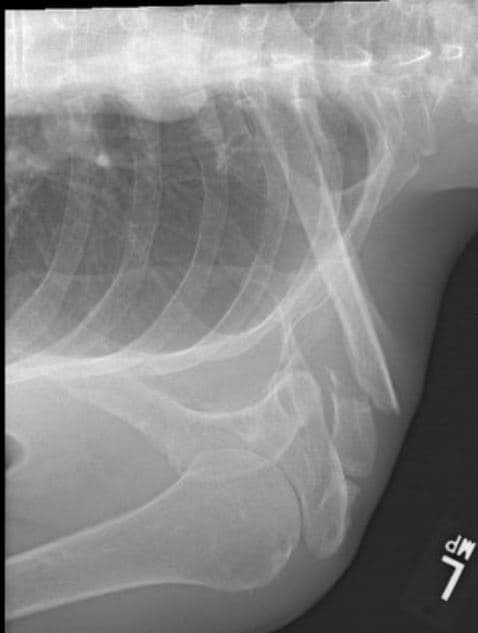

How would you describe the fracture?

Name the type of fracture

List ALL the bones present

What may have caused the abnormality?

Are these bones axial, appendicular, or both?